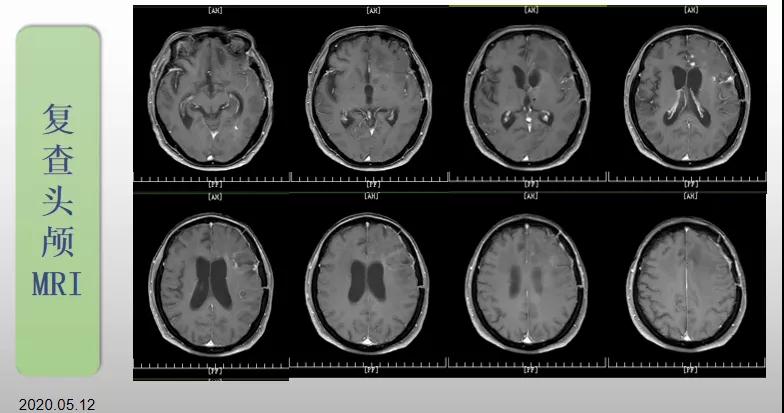

綜合治療 電場治療助70歲患者回歸正常生活

70歲的郝女士去年曾在外院查出“左額島葉”膠質(zhì)母細(xì)胞瘤(WHO Ⅳ級),并做了左側(cè)額島葉占位性病變切除術(shù)。術(shù)后進行了同步放化療。由于治療條件有限,郝女士慕名來到我院就診。賀世明主任率領(lǐng)醫(yī)護團隊立即為郝女士進行了全面的檢查,決定為其進行綜合治療 電場治療。經(jīng)過三個多月的綜合治療,患者復(fù)查頭顱MRI病變較前明顯縮小。出院時,郝女士神志清醒,睡眠飲食正常,說話很流利?!拔沂翘芍M來的,現(xiàn)在不用人攙扶,自己就可以走出病房了?!焙屡坷t(yī)護人員的手說。